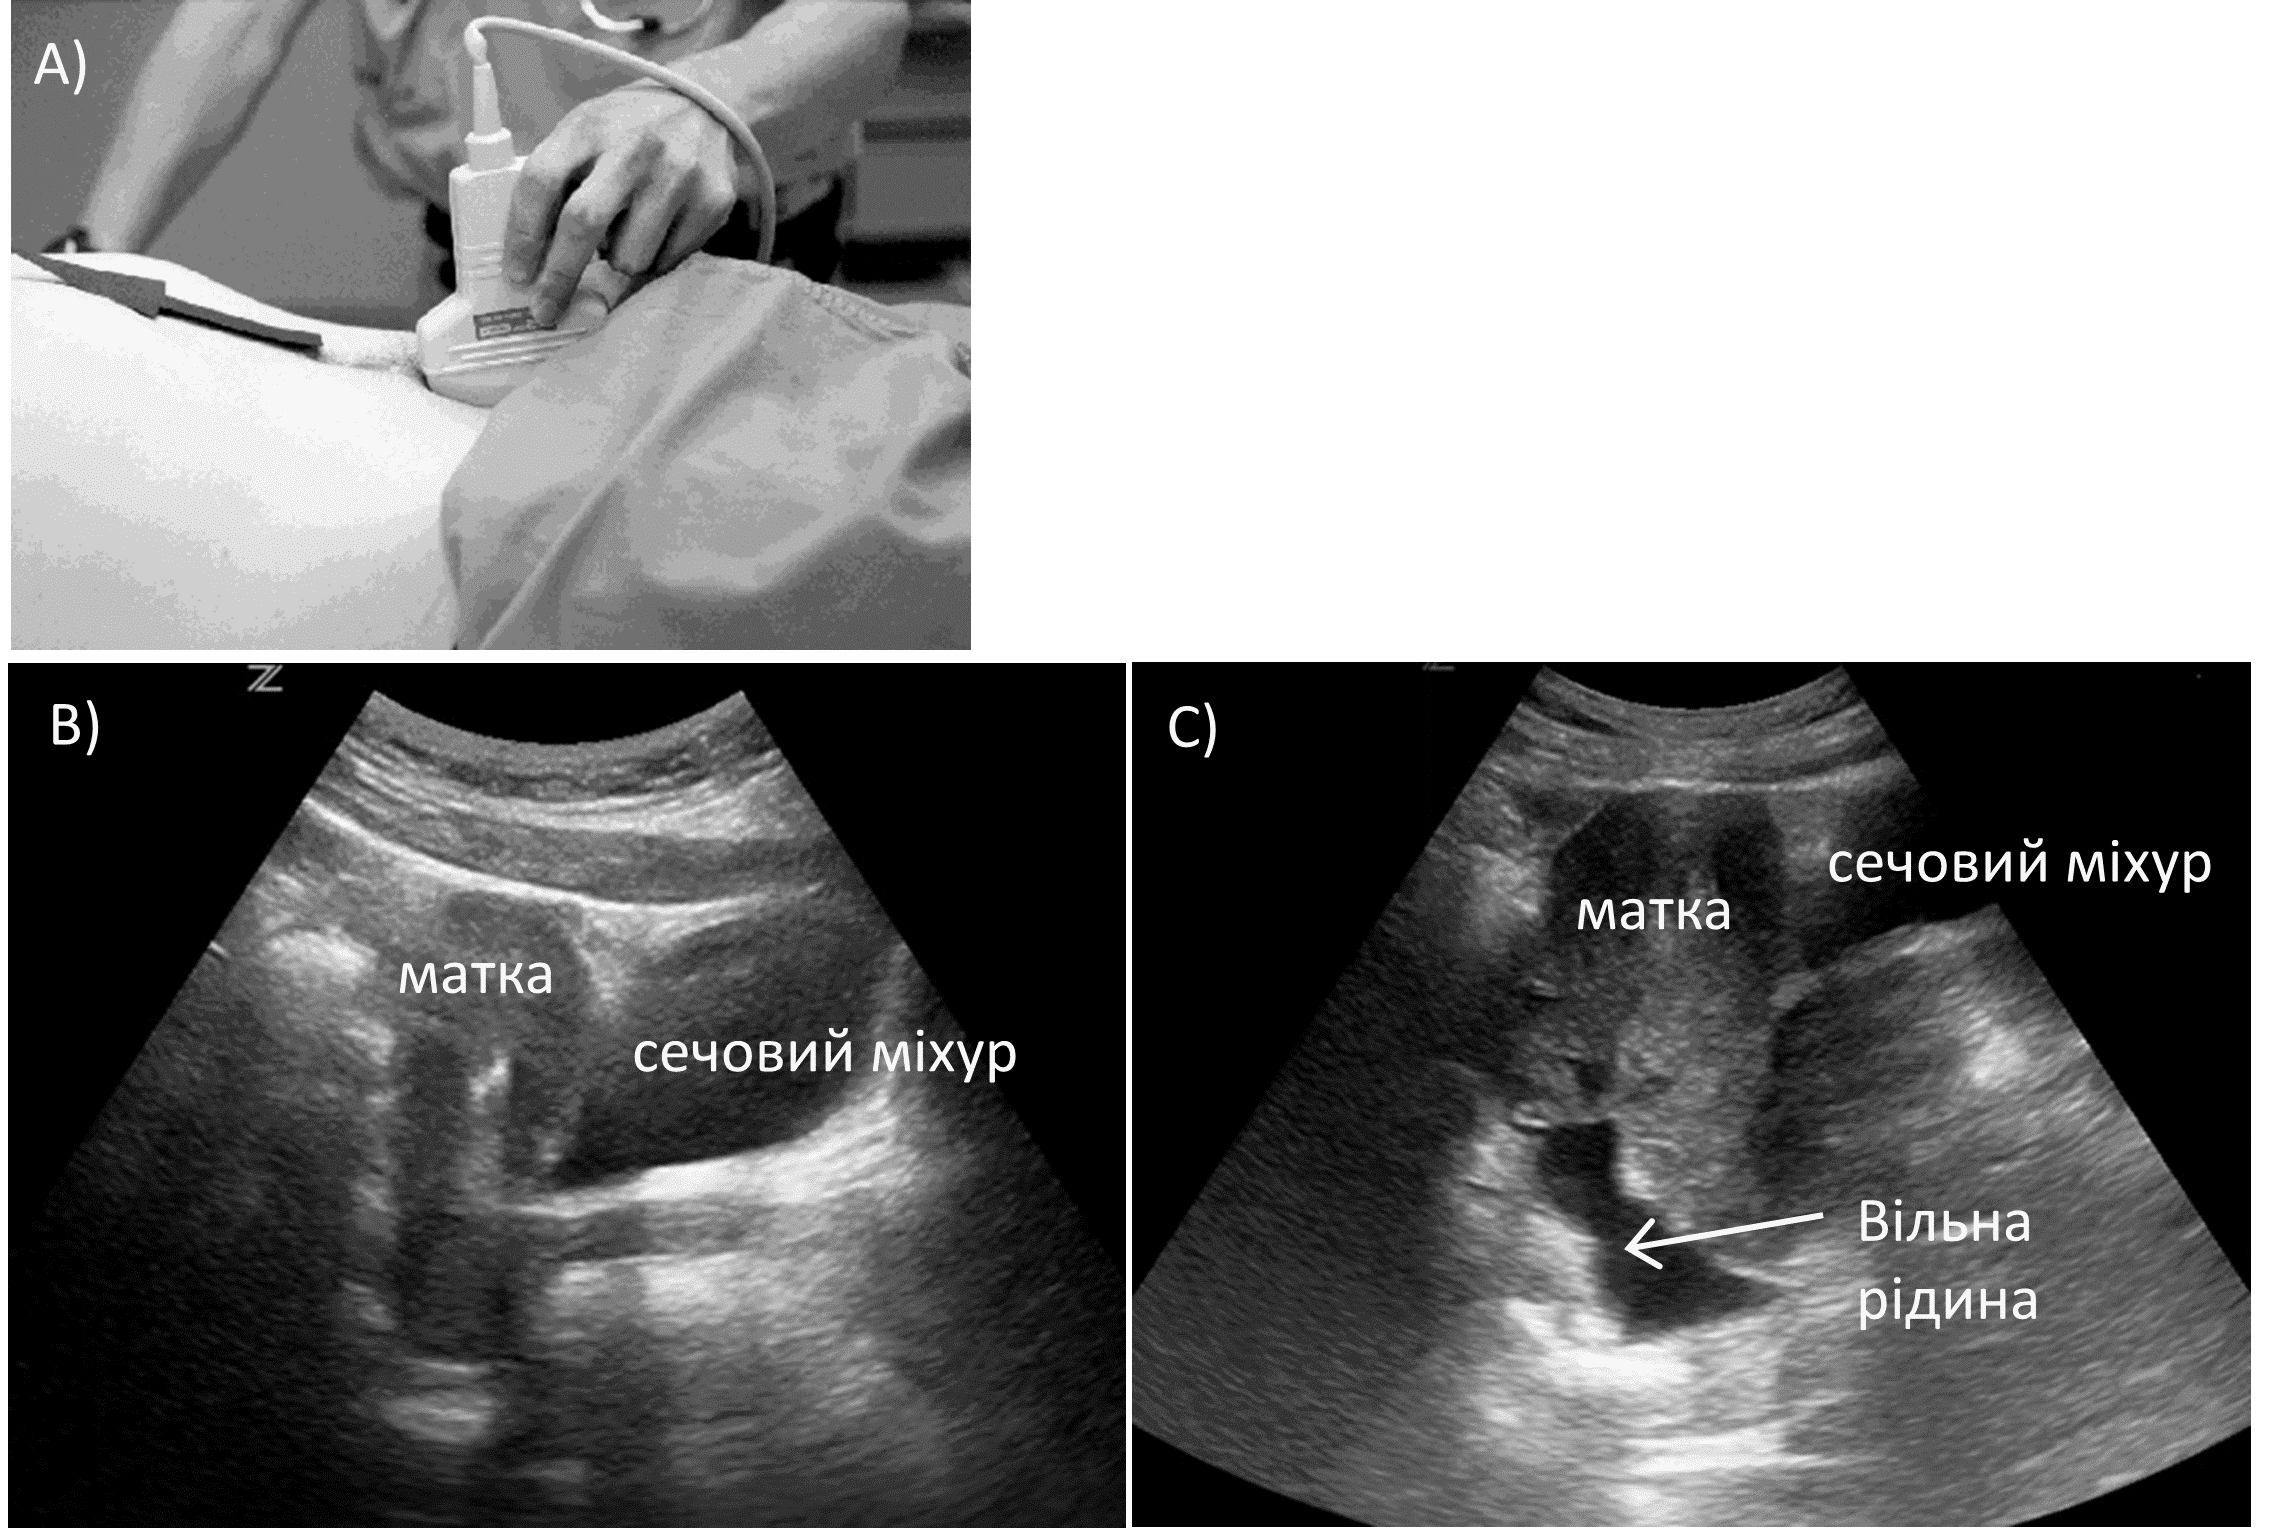

Таз є найбільш низькою діялнкою черевної порожнини і може бути найпершим місцем накопичення рідини. Тазова проекція отримується при розміщенні датчика трохи вище лобкового симфізу з маркером, спрямованим у бік голови пацієнта. Це забезпечує сагітальну картину сечового міхура. Потім зонд пересувають з боку в бік, щоб визначити наявність рідини за сечовим міхуром (зобр 7).

Зобр. 7. Сагітальний тазова проекція.

A) Розміщення датчика. B) Норма. C) Позитивний FAST з вільною рідиною.

Важливо візуалізувати лобковий симфіз (який виглядає як гіперехогенна структура), оскільки сечовий міхур може визначатися попереду від нього. Знову ж таки, як і в усіх інших проекціях при FAST, віялоподібні рухи датчиком можуть допомогти отримати краще зображення та підвищити чутливість. Поворот датчика в поперечному положенні з маркером, спрямованим праворуч від пацієнта, забезпечить осьову орієнтацію сечового міхура та може допомогти визначити рідину з обох боків, а також викривлення самого сечового міхура. Пустий сечовий міхур погіршує візуалізацію малих об’ємів тазової рідини.

Якщо у пацієнта встановлено катетер Фолея, сечовий міхур можна наповнити 200 мл стерильного фізіологічного розчину для створення сонографічного вікна. Дугласів простір є найбільш чутливою ділянкою тазу у жінок.